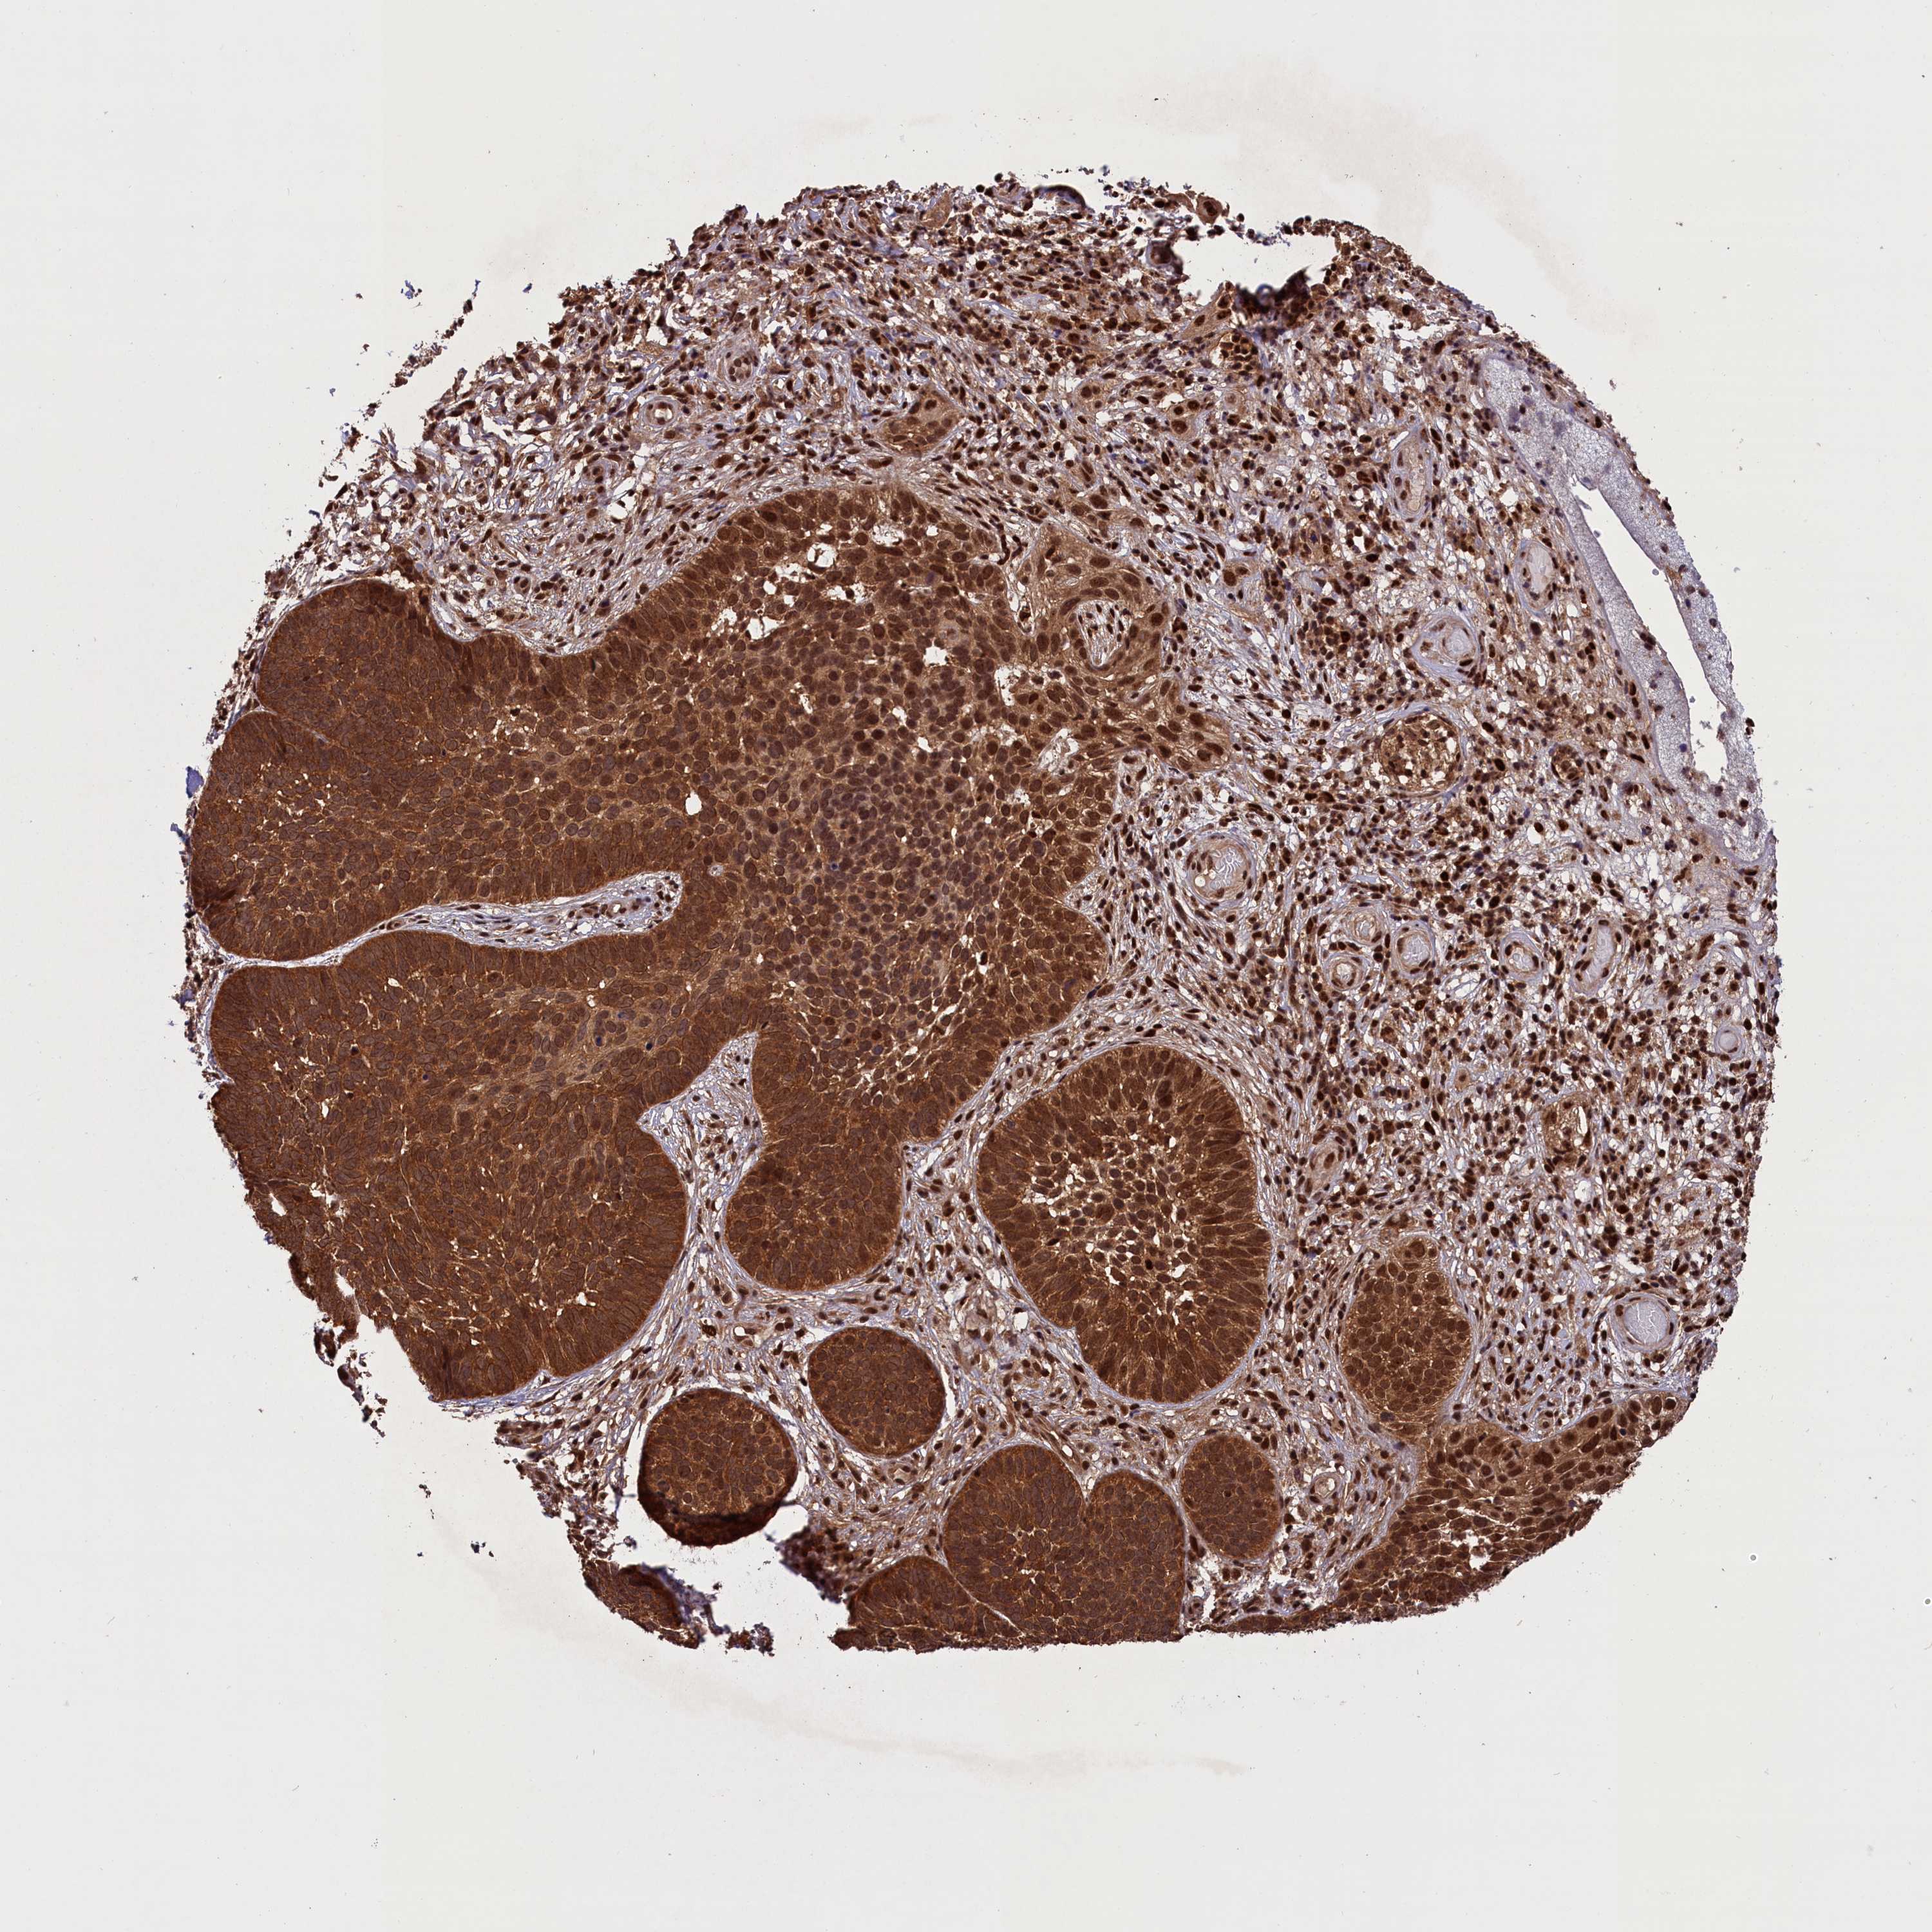

CANCER SKIN CANCER Show tissue menu

SKIN CANCER - Protein expressioni

A mouse-over function shows sample information and annotation data. Click on an image to view it in a full screen mode. Samples can be filtered based on level of antibody staining by selecting one or several of the following categories: high, medium, low and not detected. The assay and annotation is described here.

Each image is clickable and will lead to virtual microscopy that enables deeper exploration of all samples and also displays staining intensity scores, fraction scores and subcellular localization as well as patient and tissue information for each sample.

Antibody HPA041802

Basal cell carcinoma

Squamous cell carcinoma, NOS

Squamous cell carcinoma, metastatic, NOS